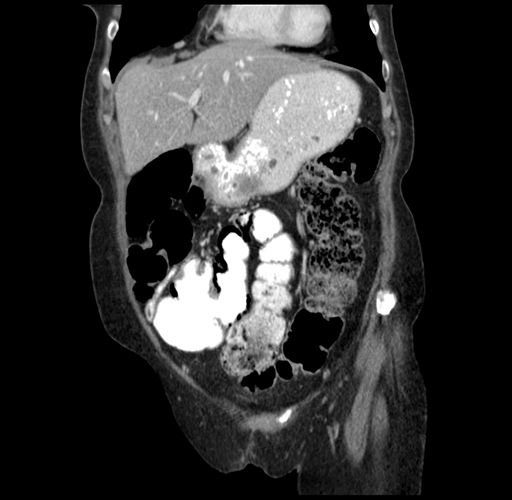

Pre-Chemo: Coronal Venous

Coronal Venous